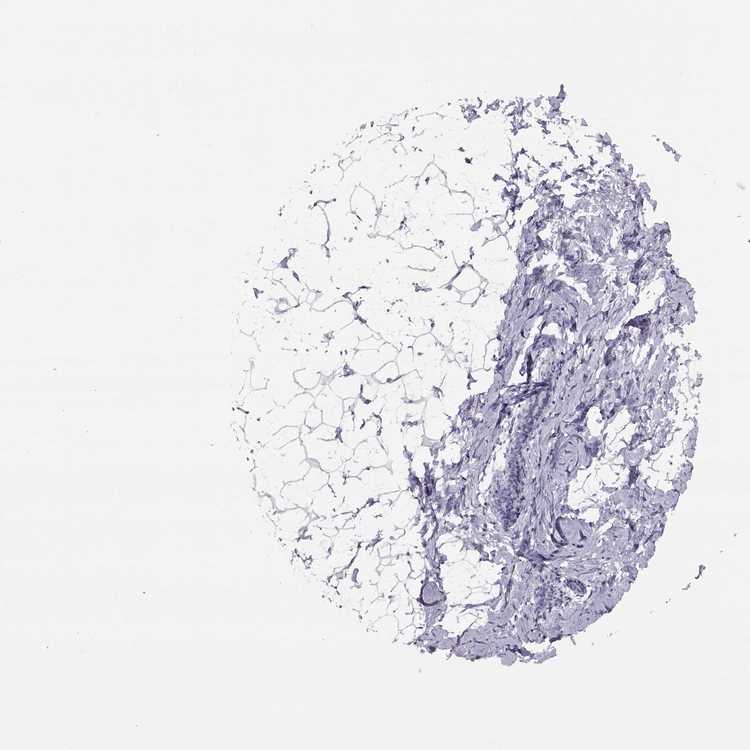

TISSUE PRIMARY DATA BREAST Show tissue menu

BREAST - Antibody stainingi

Antibody staining in the annotated cell types in the current human tissue is reported as not detected, low, medium, or high, based on conventional immunohistochemistry profiling in selected tissues. This score is based on the combination of the staining intensity and fraction of stained cells.

Each image is clickable and will lead to virtual microscopy that enables deeper exploration of all samples and also displays staining intensity scores, fraction scores and subcellular localization as well as patient and tissue information for each sample.

Antibody HPA035510

Adipocytes Not detected

Glandular cells Not detected

Myoepithelial cells Not detected